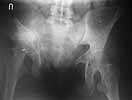

A female 27 years old admitted to our unit. Injured 18 month ago in a car accident. Initially the pelvis was fixed by anterior frame. 1 month later hardware was removed because of pin tract infection, and walk with cruches allowed. Also reptroperitoneal haematoma got infected.

She was referred to our unit 3 month ago. There was a perineal sinus, so she was sent back to her local surgical hospital, where the sinus was debrided, and about 1 liter of pus removed from the femur. The sinus closed 6 weeks ago. She walked with crutches.

Now there is shortening ~5 cm, no walking aids, of course obvious limp. No signs of infection neither clinically nor in lab tests. Which is optimal management for now? Only to move down the acetabulum (by which approach?), or full reduction of anterior and posterior aspects, acutely or gradually?